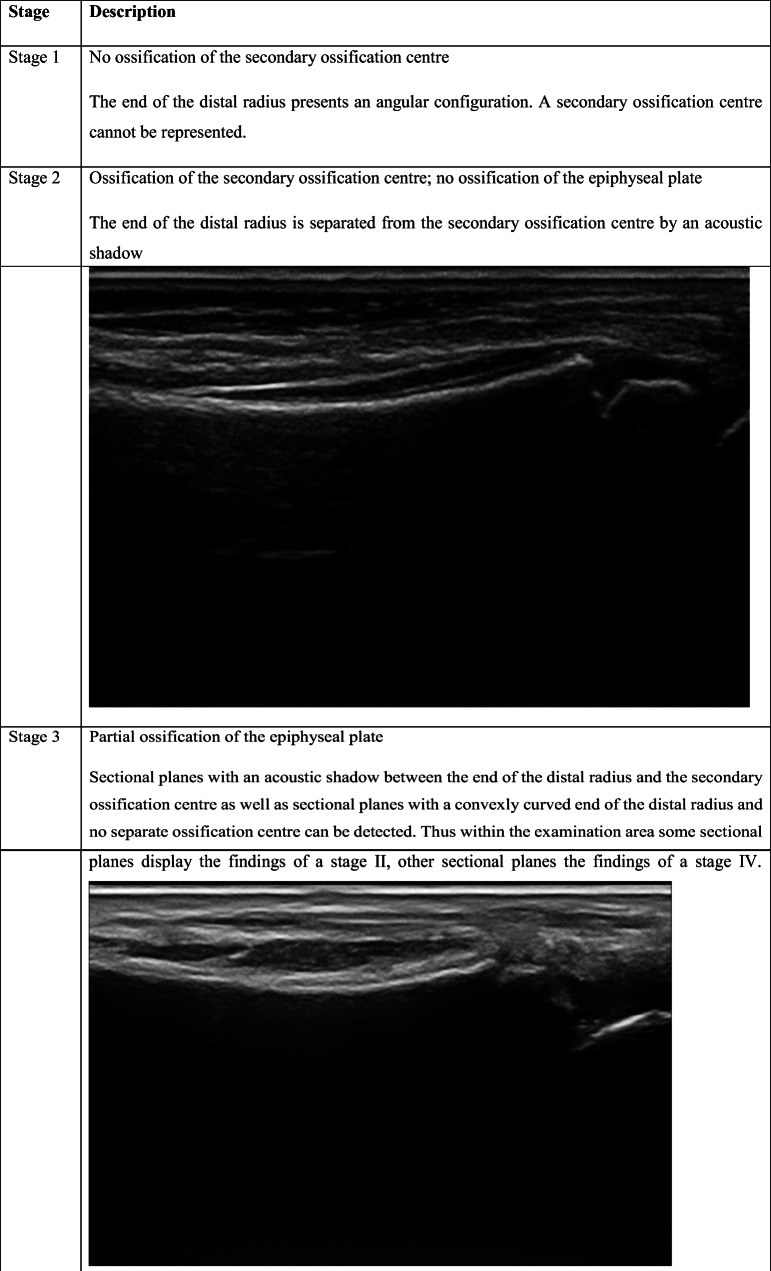

As shown in Table 2, the staging system described by Schulz et al. [27] for the clavicle, modified by Schmidt et al. [25] for the distal radius, was used.

Overlap is among the reported limitations of the USG method [2, 29]. Anatomical features that differ with age may prevent the evaluation of ossification depending on the area studied [2, 29]. Forensic age estimation for the wrist as well as clinically based studies are available, and it is known that the distal radial epiphysis is well defined on USG images [21, 22, 37]. According to the experience obtained in this study, the echogenic view of the secondary ossification center and the acoustic shadow formed are also observed along the bone surface of distal radius. When ossification between the distal of radius and the secondary ossification center has not occurred, there is no continuity on the bone surface. For this reason, the acoustic shadow does not appear in stage 2. When the integrity and consequently continuity of the bone cortex occurs in the areas with ossification, the acoustic shadow is continuously observed in these parts in stage 4. In addition, due to centrifugal ossification, there are areas where the continuity of the bone surface is formed and not yet formed. Therefore, it is seen that there is or does not have acoustic shadow in these areas. This imaging feature helps to discriminate stage 3 from stage 2 and 4. Ultrasonography offers the opportunity to evaluate different planes simultaneously during the examination. At the same time, it provides the opportunity to re-evaluate without time limitation areas where it is suspected to be reproducible. In addition to constituting a real-time review, the entire examination can be recorded in video format, allowing for later evaluation, owing to today’s developing PACS (picture archiving and communication system) capabilities. The images obtained within the scope of a standardized examination allow later evaluation by other experts on the subject.